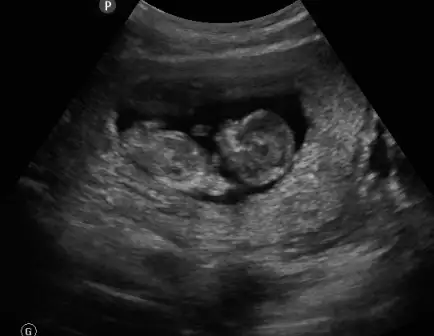

dr soylemeden siz gorun genital nub teorisi ( bebegin cinsiyeti)

Merhaba kızlar ben de uzun zamandır sizleri takip ediyorum dayanamadım üye oldum sonunda. :) Bu da bizim dünkü ultrason görüntümüz burada 12+4 günlük sizce cinsiyeti nedir?